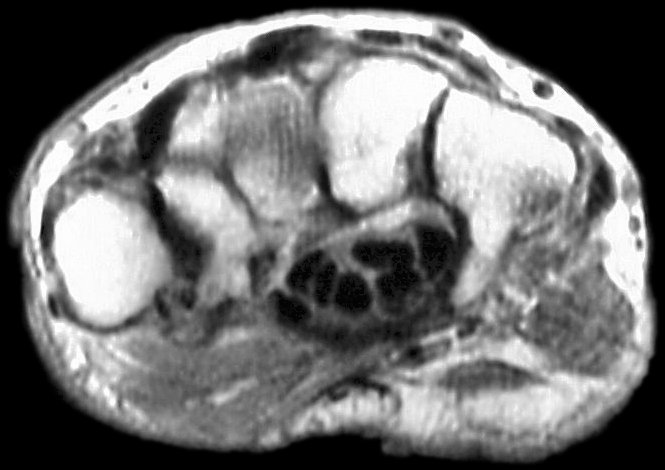

Sections through the carpal tunnel -  looking for a hook of hamate fracture or tendon discontinuity - were read as normal, although there may be a subtle signal irregularity through the hook of the hamate:

Click for larger image